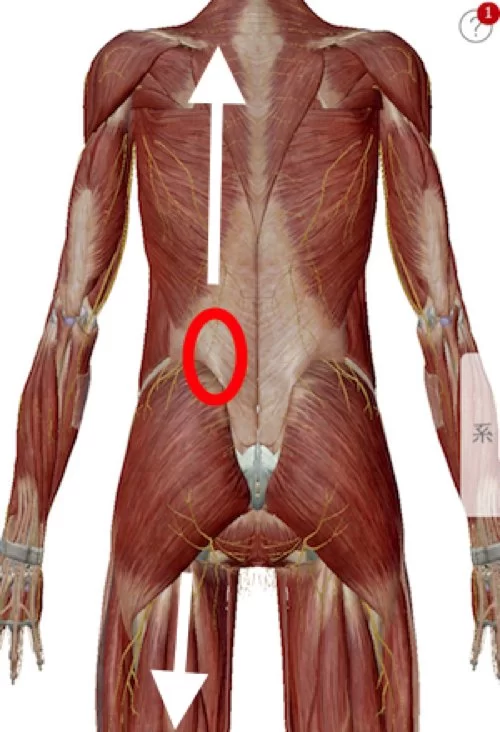

今回のお客様はちょうどこんな感じで背中と太腿の筋肉が硬直していて

腰を上からも下からも引っ張っている状態。

痛みの主な原因はこの硬直によって骨盤が引っ張られてヨジレが生まれ

ヨジレた筋肉などが神経に当たって痛い。

僕はそう考えています。

施術はまず背中の硬直を解いていくことから行いました。

脊柱起立筋群。

そして背骨と骨盤の前側を繋いでいる筋肉の硬直を解きます。

大腰筋や腸骨筋類。

それから骨盤から膝に繋がる筋肉。

そして膝から足の裏に繋がる筋肉。

最後に足裏の屈筋群を調えて施術は終了です。